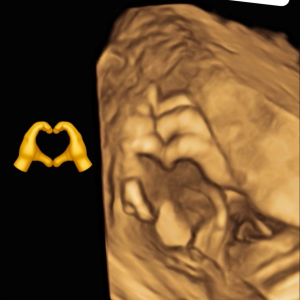

Diplômée en Echographie foetale et Gynécologique

Agrément National pour la réalisation des échographies du Premier Trimestre de grossesse

Membre du Collège d'Echographie Foetale Français (CFEF)